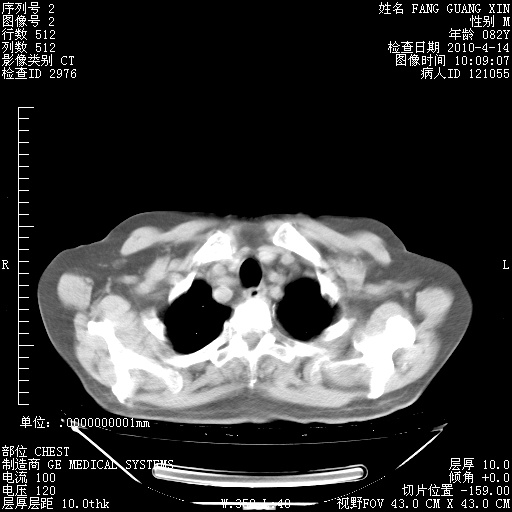

4月14日肺部CT